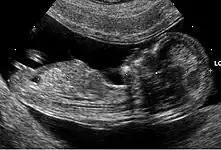

Les anomalies échographiques sont également prises en compte. Il s'agit de la recherche de malformations classiques de la trisomie 21 (comme les malformations cardiaques) et aussi de «marqueurs dont le plus important est l'épaisseur de la clarté nucale. D'autres signes sont discutés car difficiles à mesurer avec des résultats variables selon les observateurs. Toutefois, à la fin des années 2000, la combinaison entre la mesure de la clarté nucale et l'âge maternel est considérée comme un marqueur puissant d'une probabilité de trisomie 21[38].

Jusqu'en 2017, si la probabilité calculée est supérieure à 1 sur 250, un examen à visée diagnostique, invasif, (amniocentèse) était proposé à la femme enceinte pour analyse du caryotype fœtal (diagnostic prénatal par ponction de liquide amniotique à partir de 19 semaines). Lorsque l'âge gestationnel est très avancé (vers la 30e semaine) un prélèvement de sang fœtal en ponctionnant le cordon ombilical peut être réalisé.